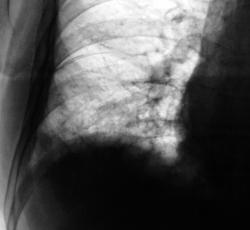

Еще через неделю, также произведен "рентген-контроль".

Сегодня произвели "очередной контроль". Произвели рентгенографию в прямой и правой боковой проекциях. Решили также произвести томографию в правой боковой проекции.